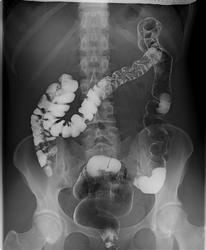

Возможно, есть изменения по-типу болезни Гирсшрунга, но неубедительно. Купол слепой кишки как бы кисетообразно подтянут по медиальному контуру, возможно есть поражение баугиниевой заслонки. Попробуйте провести энтерографию.

Никакой значимой патологии на представленных снимаках четко не определяется. То, что указано стрелками - м.б. просто спазм, м.б. и изъязвление, но не очень доказательно.

Рентгенограммы отличные, завидую (ах какая..., мне б такую). Но не люблю я это исследование, особенно в плане выискивания причин всяческих запоров. Вот и тут, я бы кроме нормы(в плане органики) ничего бы не нашел.

на мой взгляд не все изгибы разведены (может не все снимки представлены), нет тугого наполнения кишки, большая часть снимков с двойным контрастированием, да и без скопии сложно оценивать изменения указанные стрелками. а в целом без явных стойких сужений и дефектов наполнения.